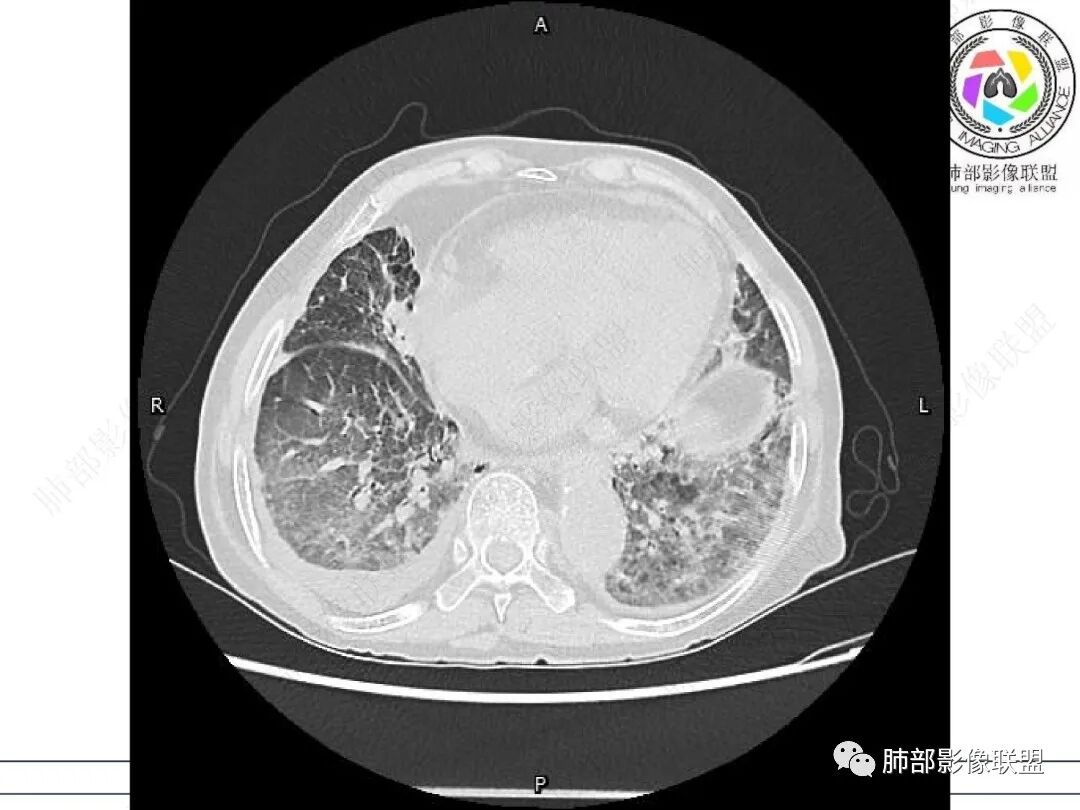

心脏大,胸腔积液,小叶间隔增厚,双肺磨玻璃影,考虑存在肺水肿,另双肺间质性炎性,类风关病史,考虑CTD-ILD,左肺上叶结核可能。

两肺叶后肋膈角区见多发蜂窝状结构破坏表现,双肺叶小叶间隔增厚,左肺上叶后段及舌段和右肺中叶胸膜炎性肉芽肿特点,双侧胸腔少量积液,有类风湿性关节炎治疗史,结缔组织相关性间质性肺病。

发热,有类风湿性关节炎、糖尿病基础病,长期口服激素及免疫抑制剂,双肺多发磨玻璃影及小叶间隔增厚,蜂窝影,支气管扩张考虑非特异性间质性肺炎存在,左肺上叶不规则结节影,周围长毛刺局部肺气肿,考虑慢性炎症,结合pct及crp升高考虑细菌感染,另真菌g升高考虑结合宿主因素,真菌感染需要积极排除。

老年,外阴溃疡加发热,感染指标明显有异常,血气分析,过度呼吸及低氧血症,宿主因素,糖尿病和激素,基础疾病RA。影像,双下肺体积有缩小,有蜂窝?双肺磨玻璃,多发结节,双侧胸水。树芽不明确。是否有旧片,这个患者有UIP背景,是否感染或者UIP急性加重,或者基础上合并肺栓塞及肺水肿?长期激素,没有提供CD4细胞亚群,存在2种情况,1,风湿病没有压制住,肺考虑CTD相关性间质改变,压制过猛,结合感染指标,奴卡是有可能的。激素加糖尿病,结核也带排,激素加磨玻璃加G实验阳性,PCP也带排,临床信息太少,进一步排查

老年女性,有高血压糖尿病及类风湿性关节炎病史,发病前发烧。影像学两肺弥漫性磨玻璃影及斑片影,有渗出性病变亦有间质性改变,支气管血管束增粗,有牵拉扭曲有小气管扩张及间质增厚,两肺下叶胸膜下少许蜂蜜状影。两侧胸腔积液。考虑类风湿性关节炎肺内浸润?合并真菌感染?

老年女性,类风湿关节炎病史多年。发热。以两肺下叶为主弥漫磨玻璃及网格状透亮影,透亮度减低,局部小蜂窝状改变;两肺胸膜下散在几枚实性病灶;双侧胸腔积液。考虑RA-ILDNSIP

双下肺后肋膈角区见多发蜂窝,小叶间隔增厚,磨玻璃改变,,双侧胸腔少量积液,Crp明显升高,有类风湿性关节炎,糖尿病。甲氨蝶呤,托法替布治疗。会阴溃疡。考虑:1.免疫妥协2.pcp?巨细胞病毒?3.甲氨蝶呤致肺损伤?4.Ctd-ild.

两下肺多发蜂窝状表现,双肺小叶间隔增厚,双肺磨玻璃影及部分炎性肉芽肿表现,双侧胸腔积液,有类风湿性关节炎治疗史,结缔组织相关性间质性肺病。患者C反应蛋白和降钙素原都高,是否合并细菌感染

女,71,外阴疼痛2周,发热1周。类风关、高血压、高血糖、卵巢囊肿、肠粘连、胆囊结石等病史及相关药物治疗史。胸部CT:两肺弥漫磨玻璃,血管束增粗,两下肺后肋膈角多发蜂窝,对称分布,双侧胸腔少量积液,纵隔窗心脏大血管影明显增宽。考虑混合性病变,CTD-ILD,并肺水肿?并PJP?。

双肺小叶间隔增厚+磨玻璃密度,双肺下叶胸膜下蜂窝,符合肺间质改变表现。双侧胸腔积液。患者类风湿,目前有外阴多发溃疡,血管炎-白塞氏病可能。实验室检查,C反高,和G实验阳性,考虑CTD-ILD合并感染,

双肺下叶多发蜂窝影,双肺小叶间隔增厚,双肺磨玻璃影,双侧胸腔积液,有类风湿性关节炎,考虑结缔组织相关性间质性肺病,合并感染

①影像表现复杂:较弥漫间质性改变,对称磨玻璃密度为主,小叶间隔增厚,有一定重力分布趋势,未见明显纤维化,气囊及蜂窝位于肺边缘,未见典型“月弓征”。心脏影增大,双侧胸腔积液。

这即可见于间质性肺病,也可见于真菌感染(如PJP)、病毒感染,类风湿,以及肺水肿等等。

一般而言,如存在磨玻璃密度影浑浊,有重力分布趋势,肺表面蜂窝影,胸腔积液等等,并不常见于单纯PJP,除非其他因素叠加。

患者存在肺水肿应当是合理的解释。其他旁证还有,心脏影增大,肾小球滤过率降低,双侧胸腔积液等等……